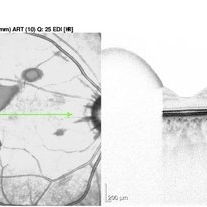

Retrohyaloid Hemorrhage OCT 2016-04-20

Sep 14 2016 by Robert T. Wendel, MD

OCT of retrohyaloid hemorrhage.

Condition/keywords: retrohyaloid hemorrhage